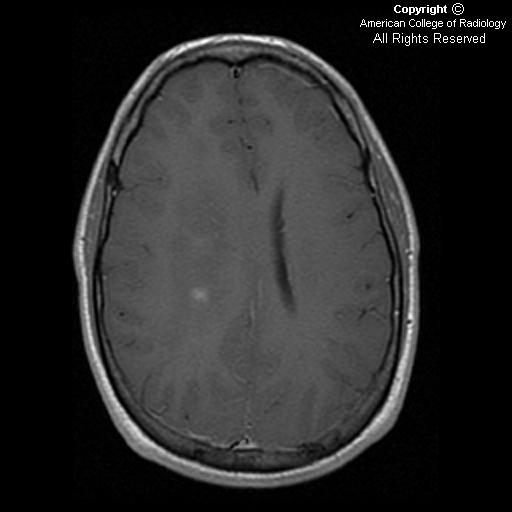

Gliomatosis cerebri is a rare growth pattern of some brain tumors, impacting at least three cerebral lobes, mostly with bilateral involvement of the cerebral hemispheres. It can be seen in some types of diffuse glioma, most notably glioblastoma. It consists of infiltrative threads that spread deeply into the brain, making them very difficult to remove with surgery or treat with radiation and is associated with poor prognosis.

As defined by the WHO, gliomatosis cerebri spans at least three cerebral lobes, usually involves both hemispheres and can also spread deeply into the gray matter or into infratentorial structures like the brainstem, cerebelleum or spinal cord.

Gliomatosis cerebri is most often caused by glioblastoma, but can also arise from astrocytoma, oligodendroglioma or other types of diffuse glioma. Other pathologies such as vasculitis, encephalitis or leukoencephalopathy may also cause similar radiological findings.